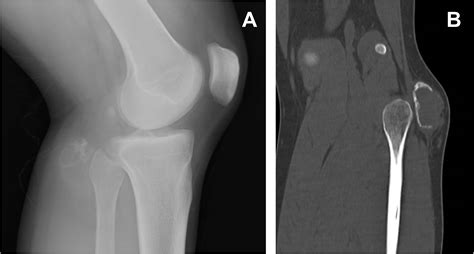

Interpreting an Osteosarcoma X Ray requires a nuanced eye. Osteosarcoma is heterogeneous, meaning it can present in several different ways depending on its subtype and location. The appearance of the lesion often depends on whether it is predominantly osteoblastic (bone-forming) or osteolytic (bone-destroying).

• MRI (Magnetic Resonance Imaging): Essential for evaluating the extent of tumor involvement in the bone marrow and soft tissues, and for surgical planning.

When reviewing an Osteosarcoma X Ray, radiologists and clinicians do not work in isolation. The imaging findings are only as valuable as the clinical story behind them. A high index of suspicion is required when the patient—most commonly an adolescent experiencing a growth spurt—reports localized, persistent pain, swelling, or a reduced range of motion in a joint, particularly around the knee (the distal femur or proximal tibia).